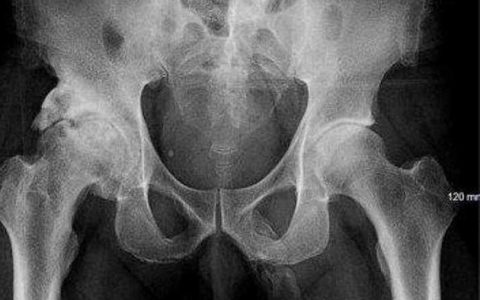

男子摔一跤竟查出生殖器骨化

国际新闻网消息 近日,英国一名身份没有公开的63岁男子手持手杖在路上行走时摔倒,一屁股坐到了地上。尽管没有撞到头,也可以在没有任何帮助的情况下站起来继续行走,但他担心膝盖受伤了。此后,他前往纽约布朗克斯区的林肯医疗和心理健康中心就诊。 在急症室,男子除了膝盖有点疼痛,他的阴茎处也有一些疼,但没有其他明显的病症,比如肿胀或有分泌物。医生决定做X光检查,来确定…